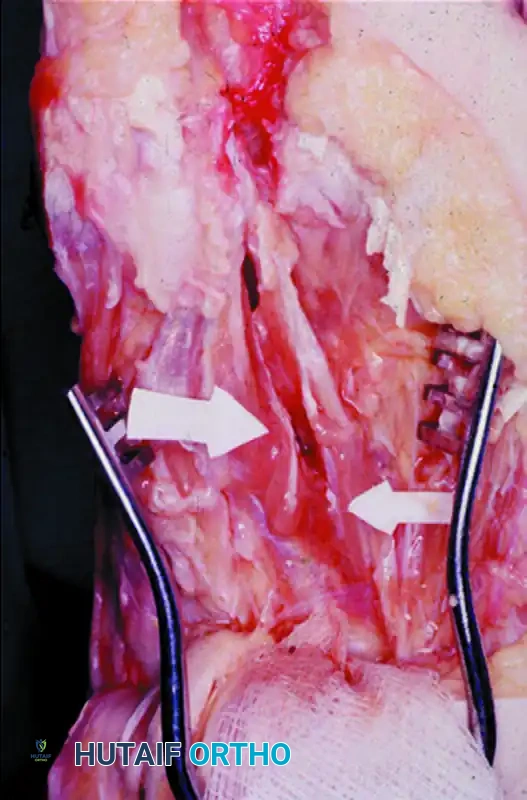

Associated Surgical & Radiographic Imaging